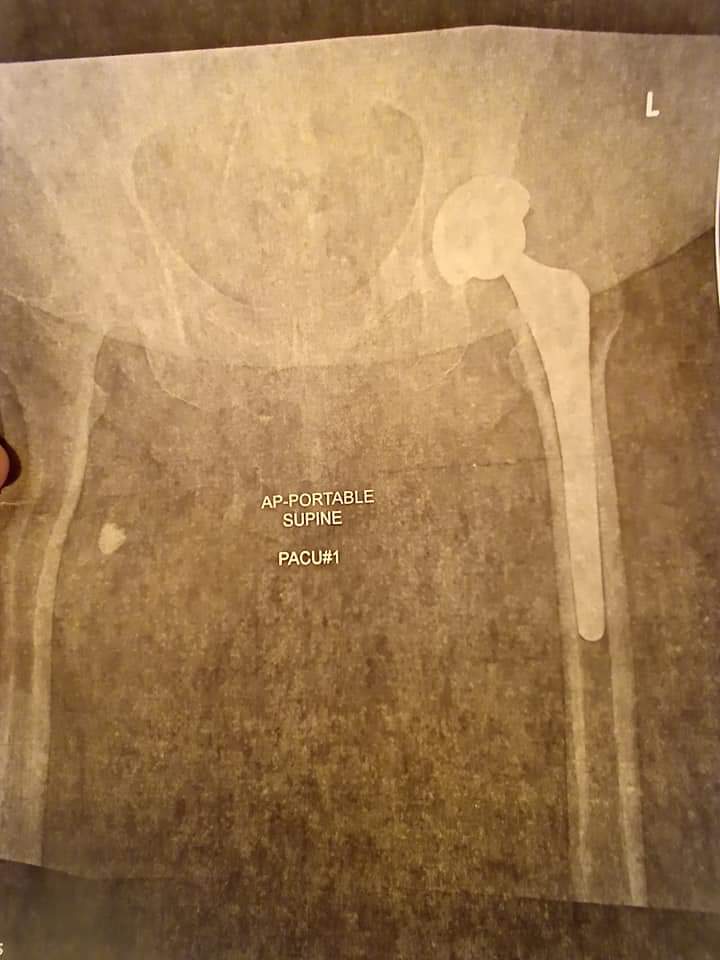

I knew HSS was the best I had heard! I called, made a appointment, got some x-rays, and was told by my physicians that they would definitely help me. They scheduled my hip replacement surgery right away.

We had a few minor setbacks during the pandemic, but before I knew it, I did all my pre-op clearance and had surgery scheduled at HSS in New York City! The facility was so neat and clean and the staff was amazing and so kind.

Pre-op was amazing. So organized and knowledgeable. Awesome anesthesiologist and team. They even helped me with my anxiety over my first surgery. "Snap", I was in and out of surgery!

What a view on the Hudson River. I had exceptional care. Sunrises and sunsets. Fabulous physical therapy. Dr. Gausden and her staff checked on me daily.